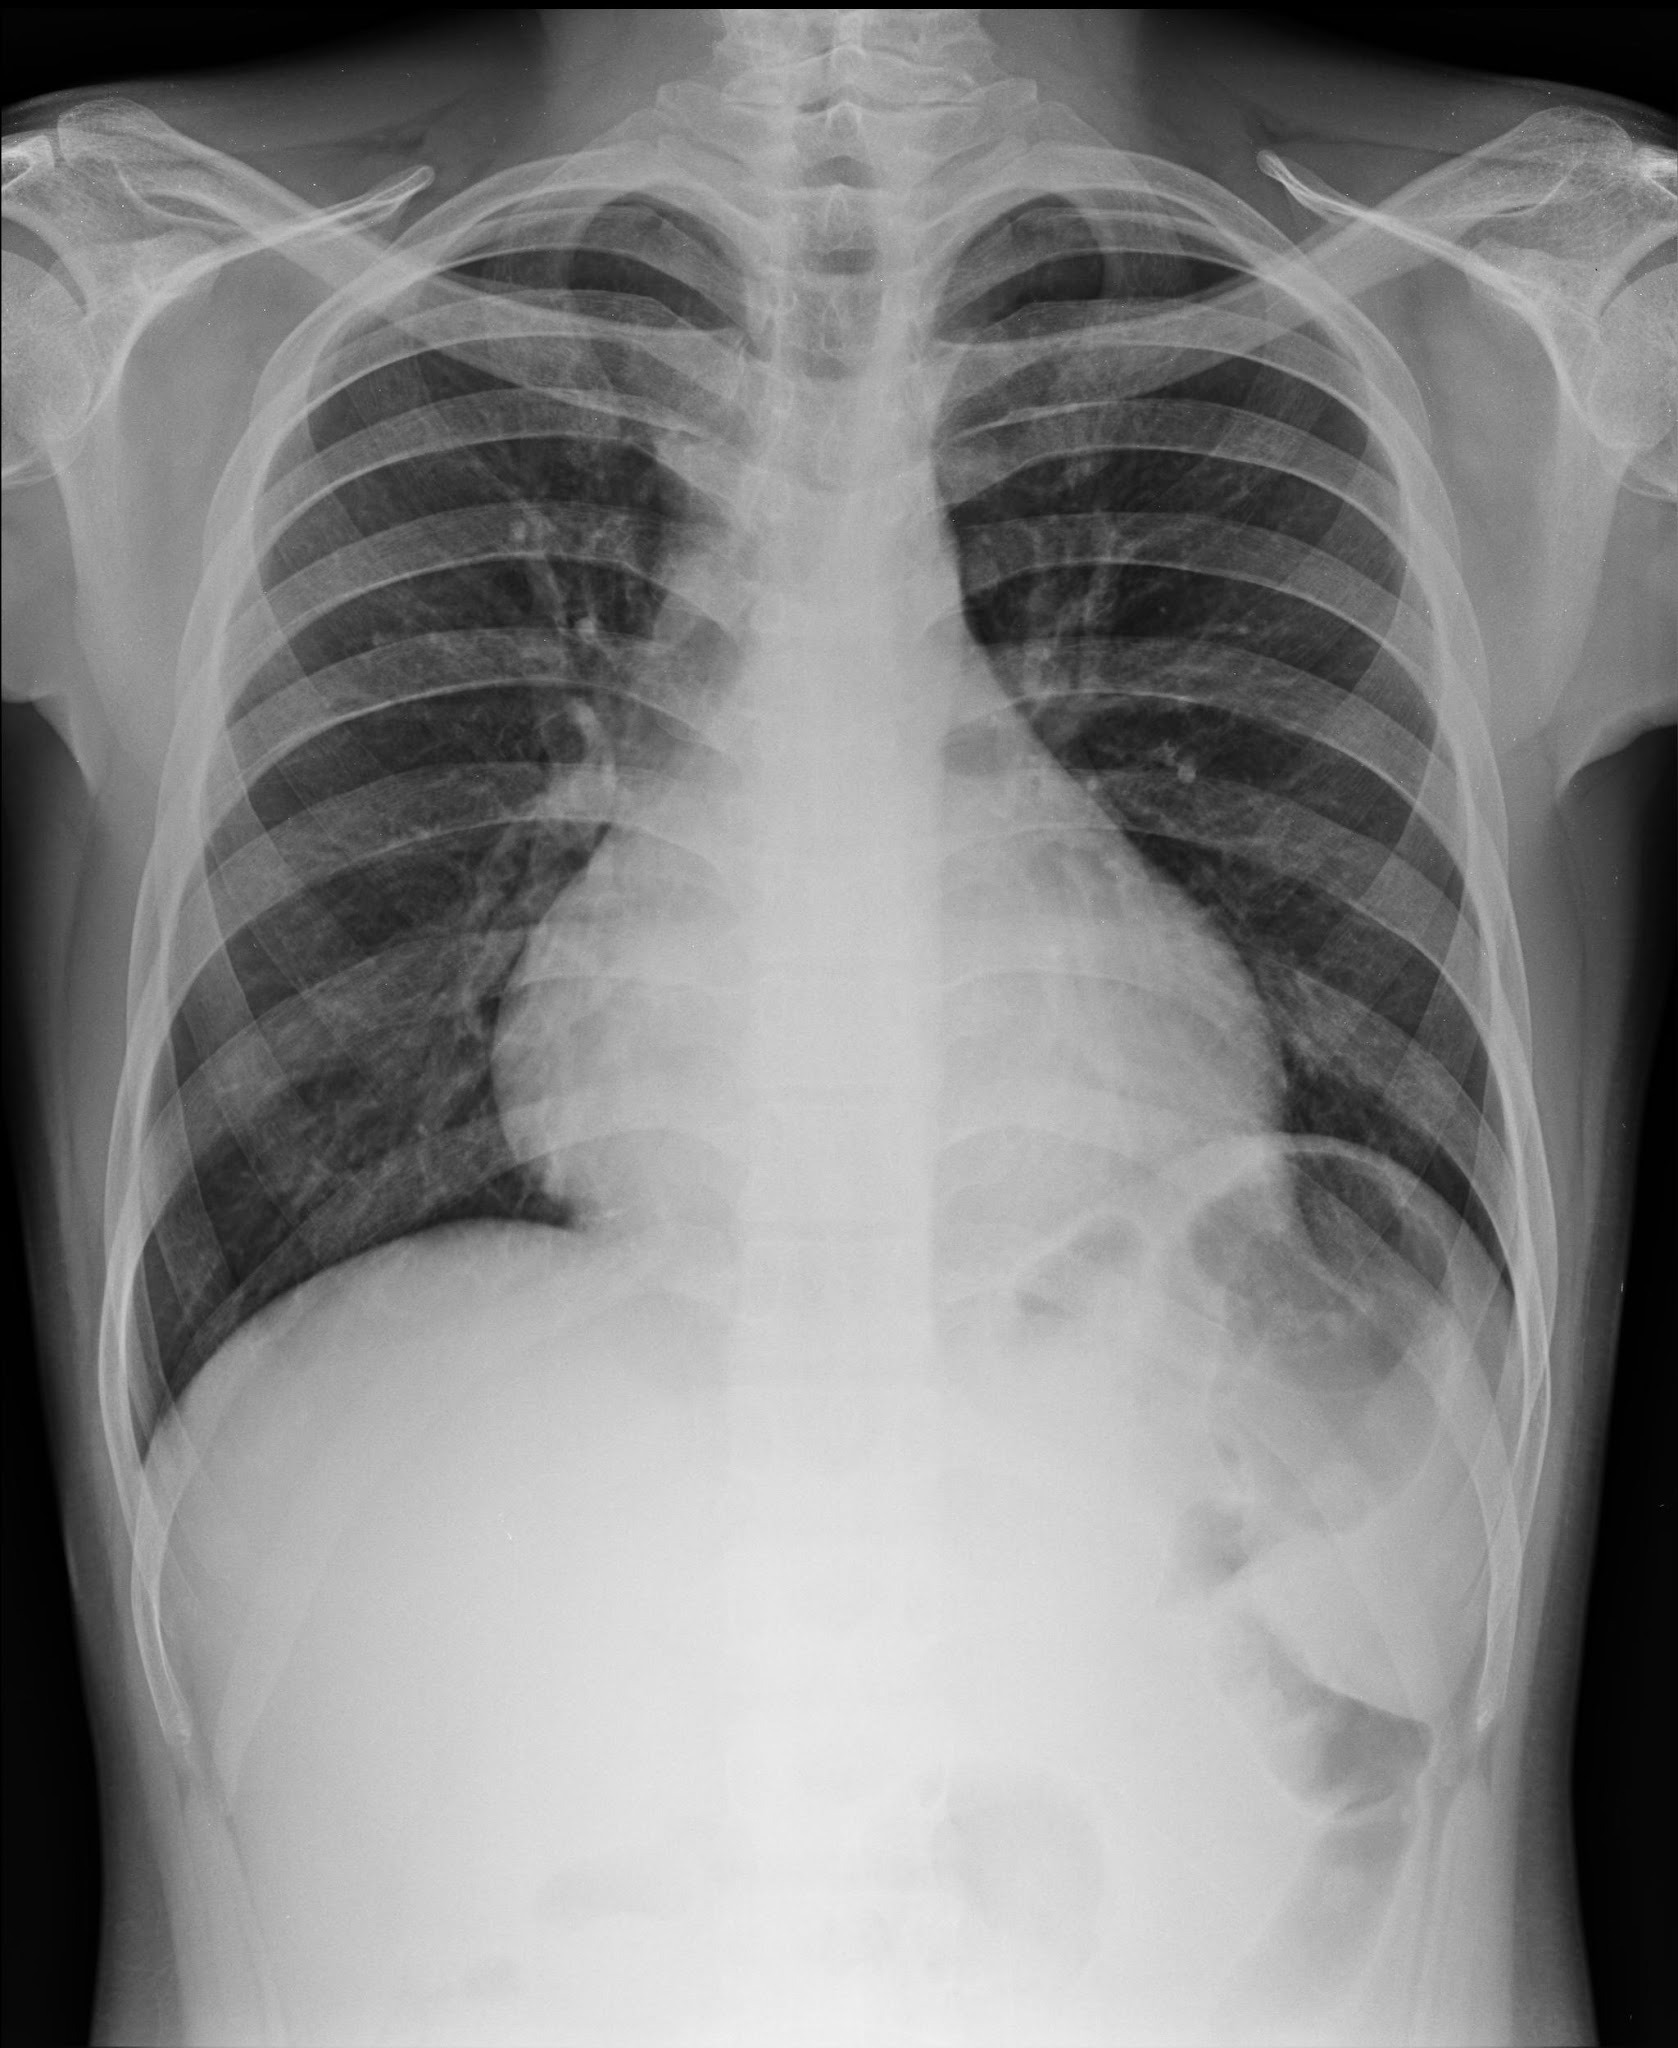

Poor Inspiration

Only eight posterior ribs are visible on this frontal chest radiograph.

A poor inspiration may “crowd” and therefore accentuate the lung markings at the bases (black arrows) and may make the heart seem larger than it actually is.